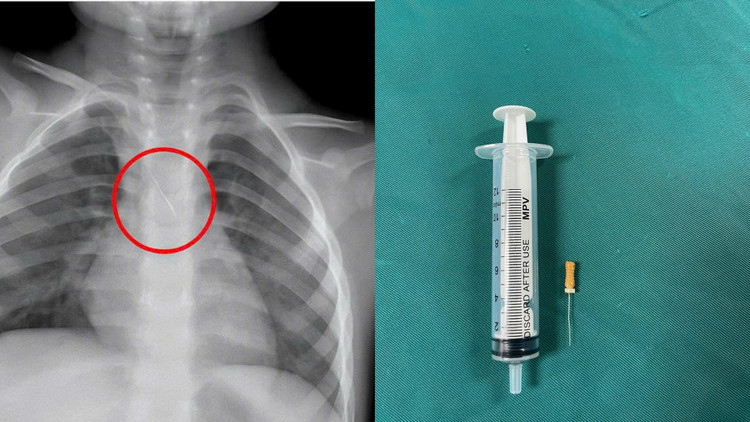

Qua thăm khám và chụp phim, các bác sĩ xác định bé bị sặc kim chọc tủy dài khoảng 22mm, vị trí mắc tại góc carina, nơi chia đôi khí quản.

Dị vật này dài khoảng 22mm, nằm ở góc carina (nơi vùng chia đôi khí quản), một đầu nhọn cắm vào 1/3 dưới khí quản, một đầu tròn nằm trong phế quản gốc trái.

Dị vật trong đường thở của bệnh nhi. Ảnh BV